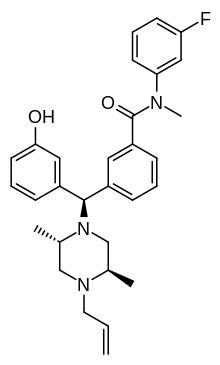

The pharmacodynamic response to an opioid depends upon the receptor to which it binds, its affinity for that receptor, and whether the opioid is an agonist or an antagonist. For example, the supraspinal analgesic properties of the opioid agonist morphine are mediated by activation of the μ1 receptor; respiratory depression and physical dependence by the μ2 receptor; and sedation and spinal analgesia by the κ receptor. Each group of opioid receptors elicits a distinct set of neurological responses, with the receptor subtypes (such as μ1 and μ2 for example) providing even more [measurably] specific responses. Unique to each opioid is its distinct binding affinity to the various classes of opioid receptors (e.g. the μ, κ, and δ opioid receptors are activated at different magnitudes according to the specific receptor binding affinities of the opioid). For example, the opiate alkaloid morphine exhibits high-affinity binding to the μ-opioid receptor, while ketazocine exhibits high affinity to ĸ receptors. It is this combinatorial mechanism that allows for such a wide class of opioids and molecular designs to exist, each with its own unique effect profile. Their individual molecular structure is also responsible for their different duration of action, whereby metabolic breakdown (such as N-dealkylation) is responsible for opioid metabolism.

A new strategy of drug development takes receptor signal transduction into consideration. This strategy strives to increase the activation of desirable signalling pathways while reducing the impact on undesirable pathways. This differential strategy has been given several names, including functional selectivity and biased agonism. The first opioid that was intentionally designed as a biased agonist and placed into clinical evaluation is the drug oliceridine. It displays analgesic activity and reduced adverse effects.[162]

Opioid comparison